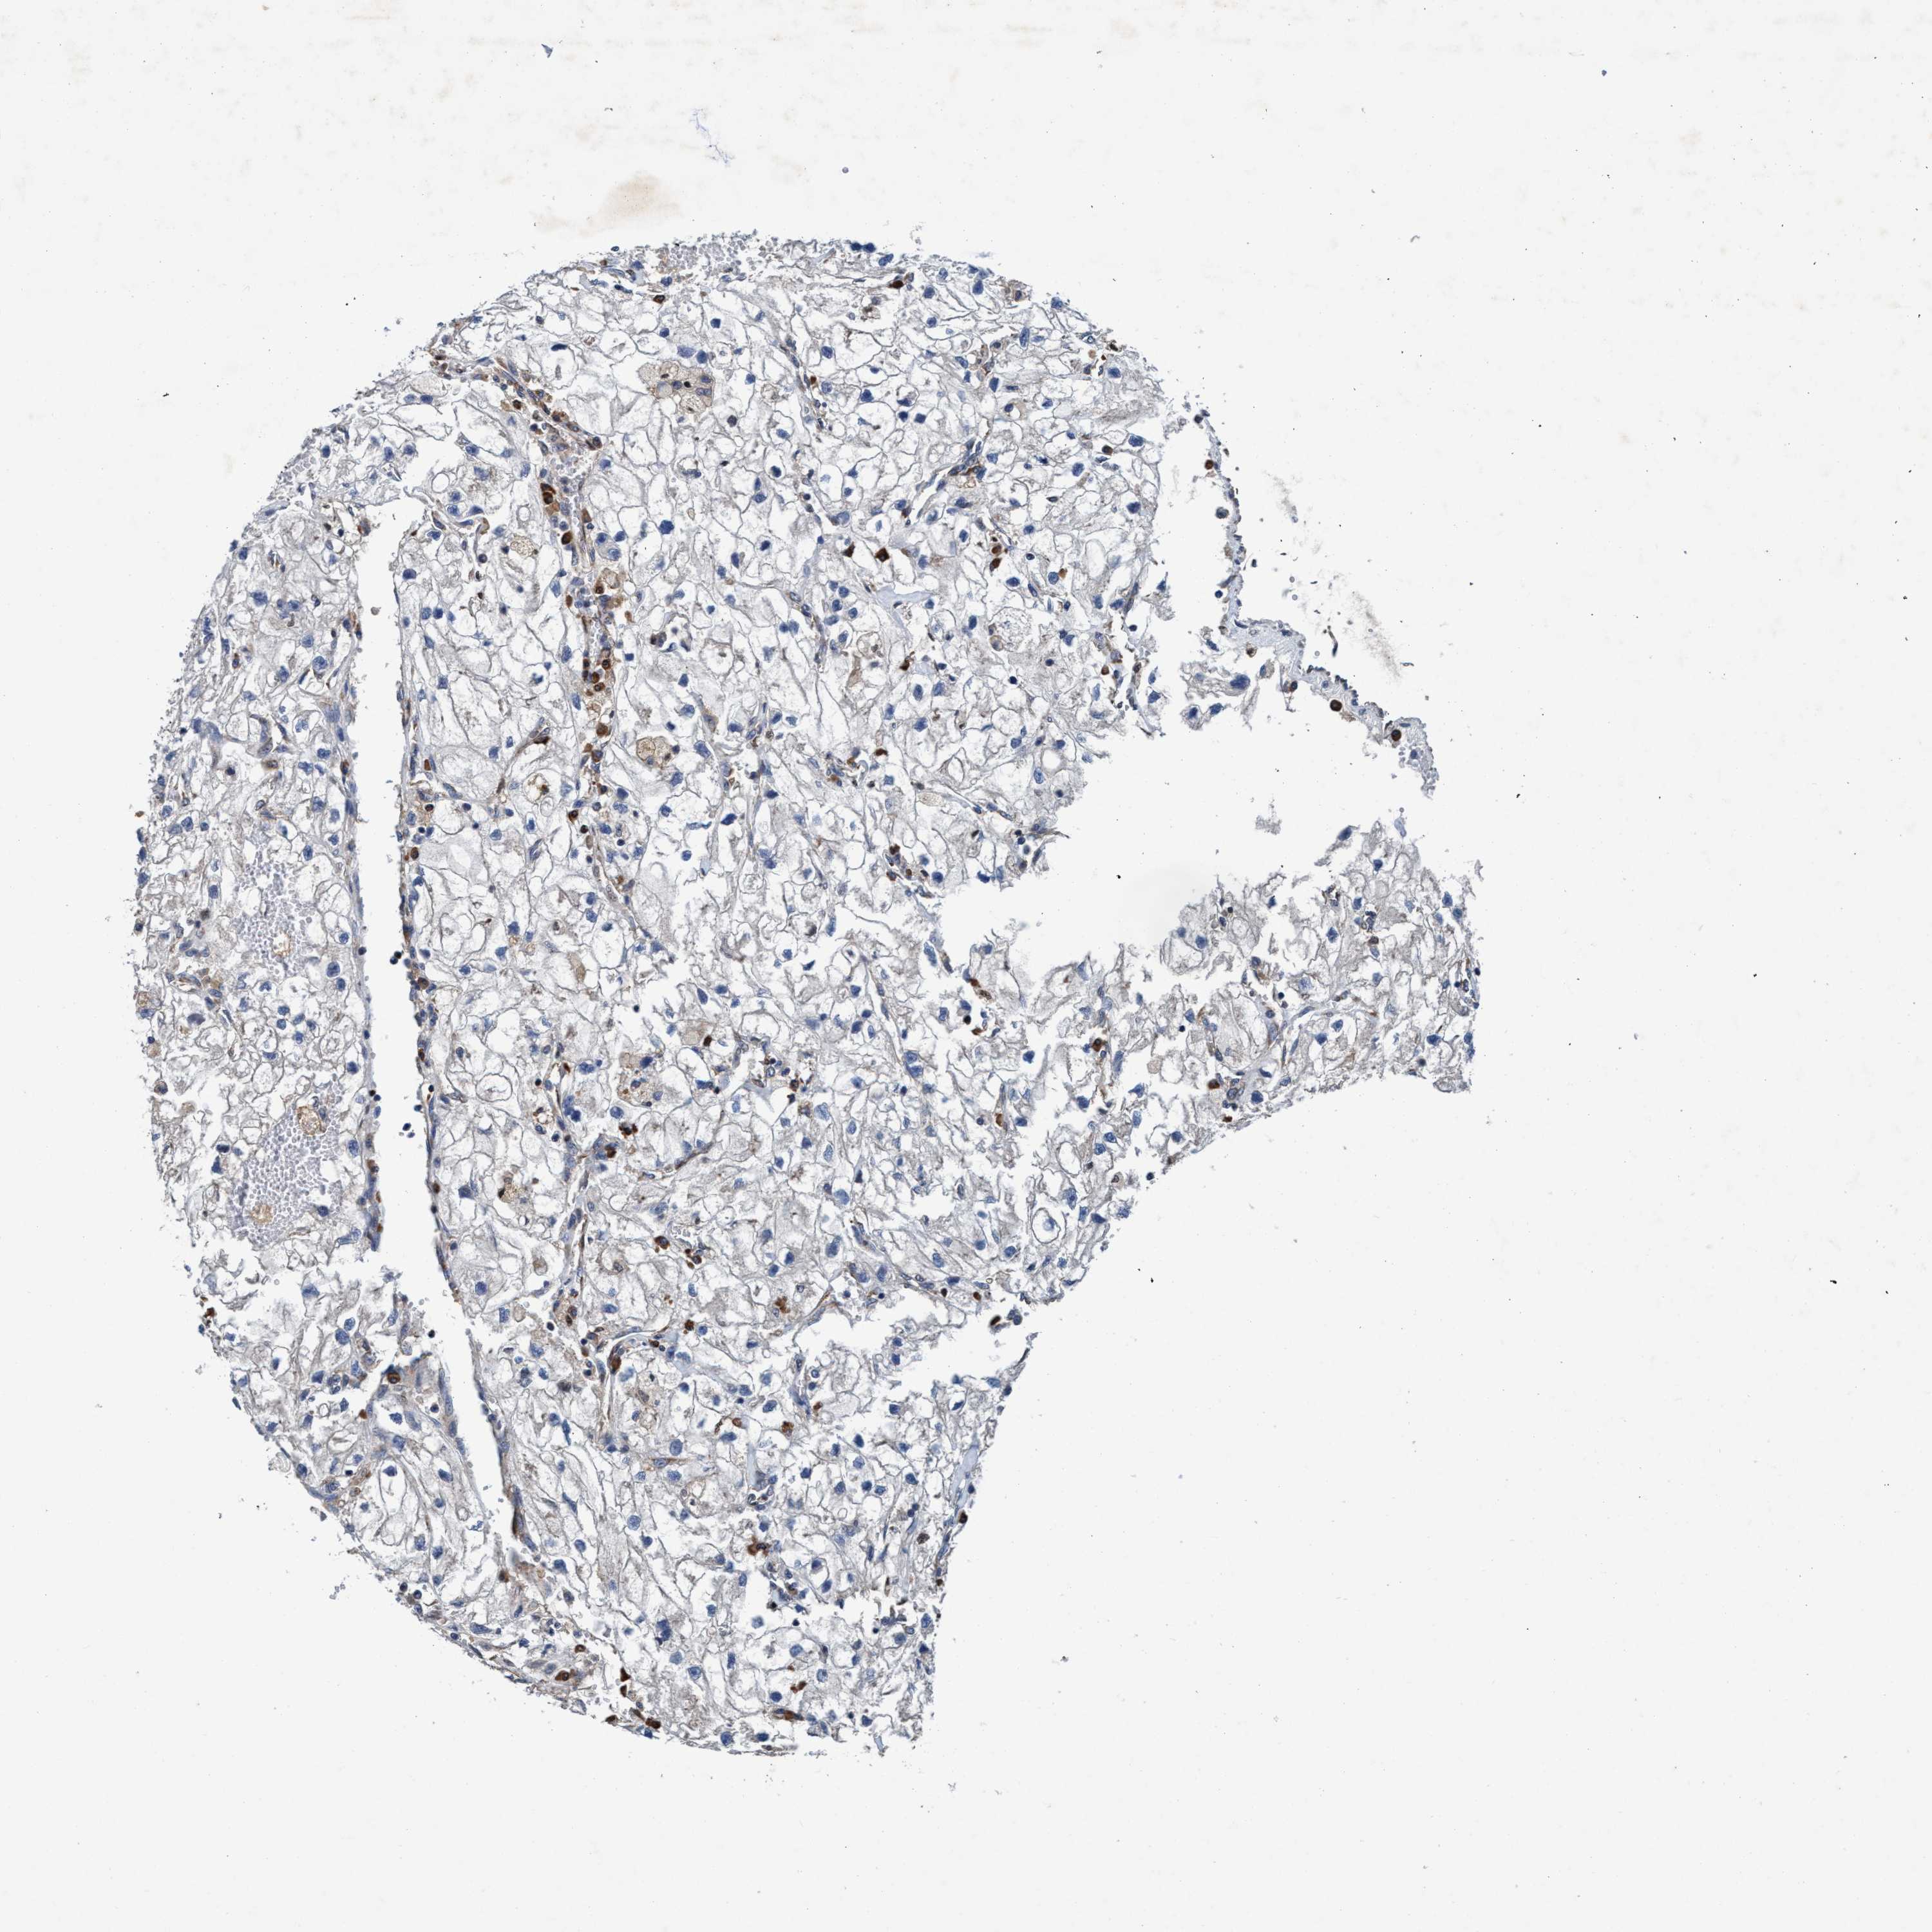

KIDNEY RENAL CLEAR CELL CARCINOMA (VALIDATION) - Interactive survival scatter ploti

The Survival Scatter plot shows the clinical status (i.e. dead or alive) for all individuals in the patient cohort, based on the same data that underlies the corresponding Kaplan-Meier plots. Patients that are alive at last time for follow-up are shown in blue and patients who have died during the study are shown in red.

The x-axis shows the expression levels (FPKM) of the investigated gene in the tumor tissue at the time of diagnosis. The y-axis shows the follow-up time after diagnosis (years). Both axes are complimented with kernel density curves demonstrating the data density over the axes. The top density plot shows the expression levels (FPKM) distribution among dead (red) and alive patients (blue). The right density plot shows the data density of the survived years of dead patients with high and low expression levels respectively, stratified using the cutoff indicated by the vertical dashed line through the Survival Scatter plot. This cutoff is automatically defined based on the FPKM cutoff that minimizes the p-score. The cutoff can be changed by dragging the vertical line or by entering a cutoff value in the square labeled "Current cut-off".

Under the Survival Scatter plot the p-score landscape (black curve; left axis) is shown together with dead median separation (red curve; right axis). Dead median separation is the difference in median mRNA expression between patients who have died with high and low expression, respectively. It is calculated as follows: median FPKM expression of dead patients with high expression - median FPKM expression of dead patients with low expression. This is intended to aid the user in visually exploring custom cutoffs and the associated p-scores and dead median separation.

Individual patient data is displayed and can be filtered by clicking on one or more of the category buttons on the top of the page. Categories describing expression level and patient information include: high, low, alive, dead, female, male and tumor stages. The scale of the x-axis can be toggled between linear and log-scale by clicking on the "x log" button. Mouse-over function shows TCGA ID, patient information and mRNA expression (FPKM) for each patient.

& Survival analysisi

Kaplan-Meier plots summarize results from analysis of correlation between mRNA expression level and patient survival. Patients were divided based on level of expression into one of the two groups "low" (under cut off) or "high" (over cut off). X-axis shows time for survival (years) and y-axis shows the probability of survival, where 1.0 corresponds to 100 percent.

ENDOG is not prognostic in Kidney Renal Clear Cell Carcinoma (validation)

Best expression cut offi

Based on the FPKM value of each gene, patients were classified into two groups and association between prognosis (survival) and gene expression (FPKM) was examined. The best expression cut-off refers the FPKM value that yields maximal difference with regard to survival between the two groups at the lowest log-rank P-value. Best expression cut-off was selected based on survival analysis .

When clicking on this number, the vertical dashed line indicating cut-off, the interactive survival plot, and the Kaplan-Meier curve will be adjusted to show results based on the best expression cut-off.

: 20.69

Median expressioni

Median expression refers to the median FPKM value calculated based on the gene expression (FPKM) data from all patients in this dataset. When clicking on this number, the vertical dashed line indicating cut-off, the interactive survival plot, and the Kaplan-Meier curve will be adjusted to show results based on the median expression.

: N/A

Median follow up timei

Median follow up time refers to the median time (years) after diagnosis with this type of cancer, based on clinical data from all patients in this dataset.

P scorei

Log-rank P value for Kaplan-Meier plot showing results from analysis of correlation between mRNA expression level and patient survival.

N/A

5-year survival highi

5-year survival for patients with higher expression than the expression cutoff.

For melanoma and glioma, 3-year survival is shown.

5-year survival lowi

5-year survival for patients with lower expression than the expression cutoff.

TCGA RNA samplesi

RNA-seq data is reported as average FPKM (number Fragments Per Kilobase of exon per Million reads), generated by the The Cancer Genome Atlas (TCGA) .

Normal distribution across the dataset is visualized with box plots, shown as median and 25th and 75th percentiles. Points are displayed as outliers if they are above or below 1.5 times the interquartile range. FPKM values of the individual samples are presented next to the box plot.

Average pTPM 14.7

Number of samples 100